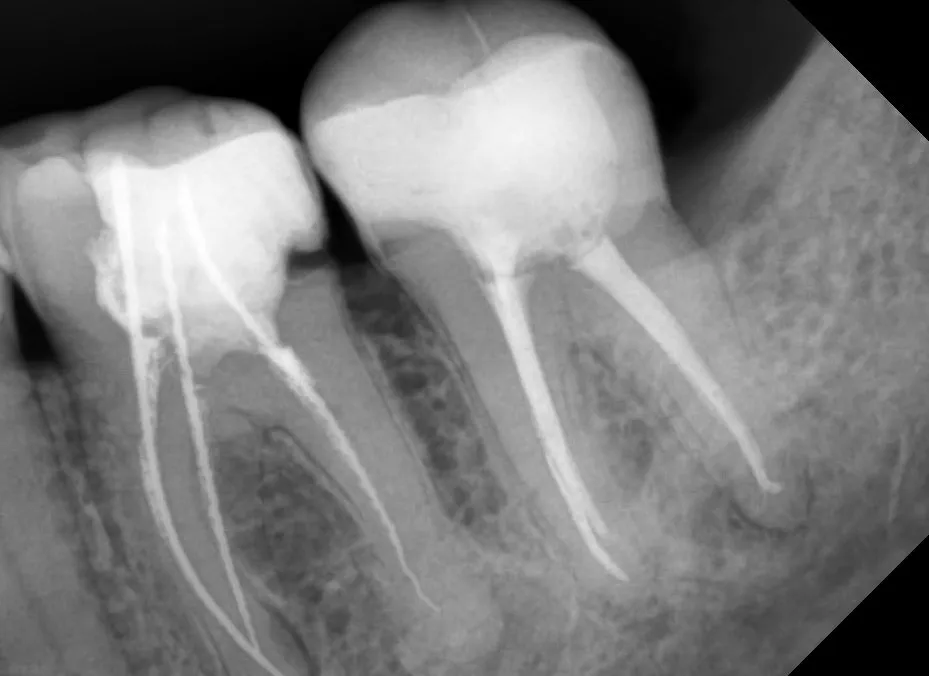

Пациент был направлен стоматологом хирургом для сохранения зуба 3.7. В ходе осмотра была произведена ревизия зуба 3.7 для оценки дальнейших действий, разрешение зуба вызванное карточным поражением.

Произведена коррекция десневого контура в дистальном отделе и восстановление для эндодонтического лечения. Произведено эндодонтическое лечение и восстановление зуба 3.7 под коронку.